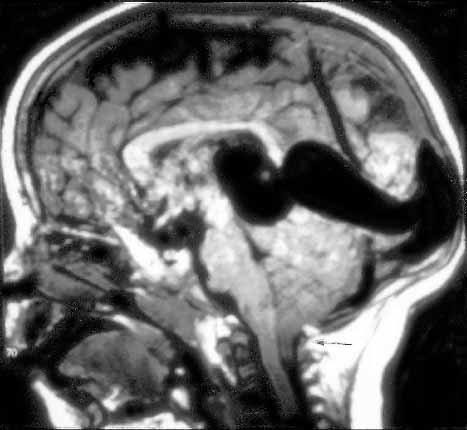

Prenatal diagnosis of cerebral vascular malformations: case series

To describe the ultrasound findings and perinatal out- comes of cases with a prenatal diagnosis of cerebral vascular malformations (CVM)